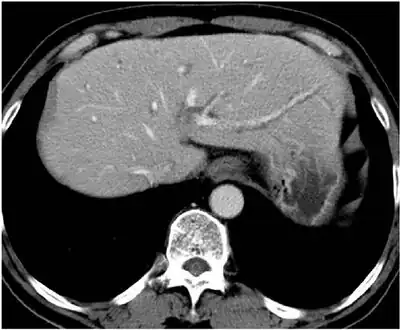

-

CT of individual with clonorchiasis -